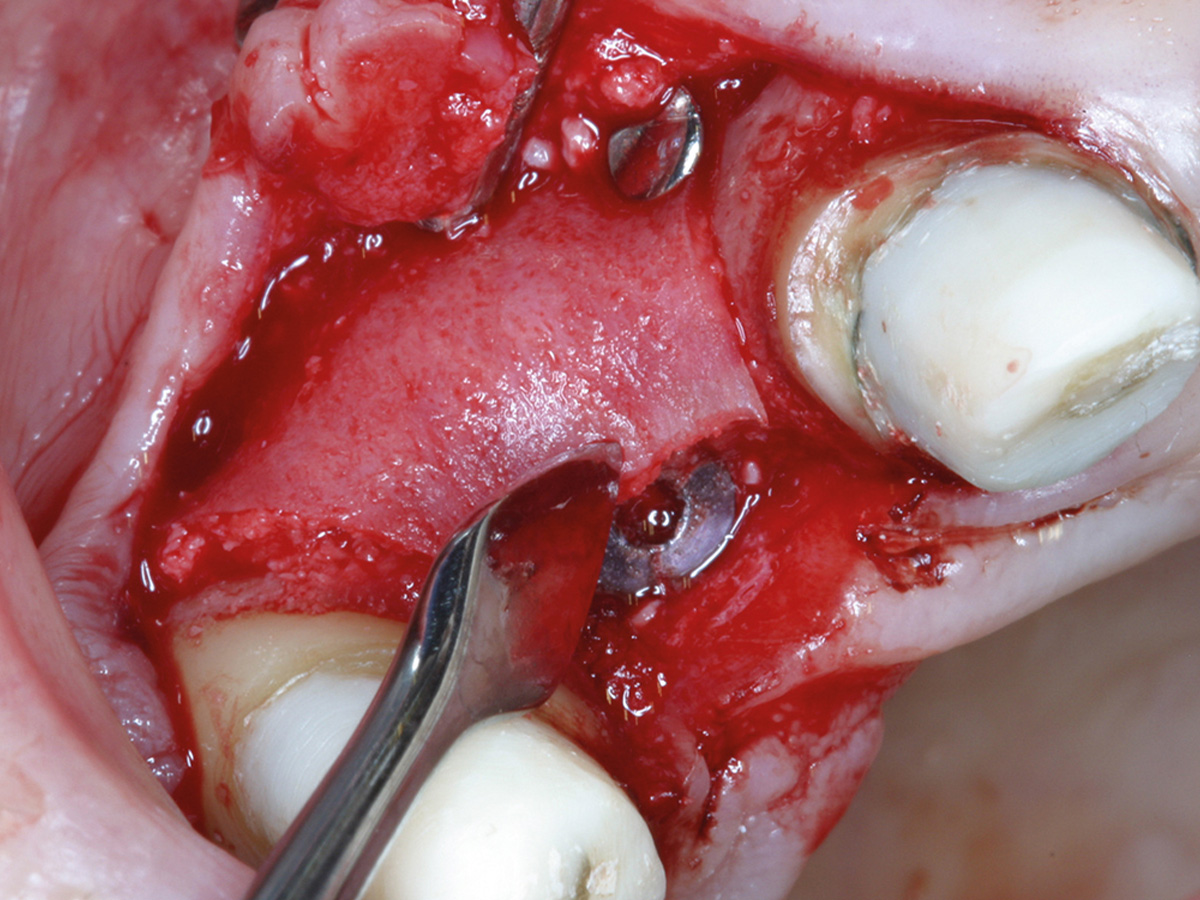

Abbildung 5a

Intraoperative Augmentation...

Abbildung 5b

nach Anfrischung des ortsständigen Knochens mit Bone Lamina/mp3...

Abbildung 5c

sowie Nagelung mit Frioss-Nägeln.